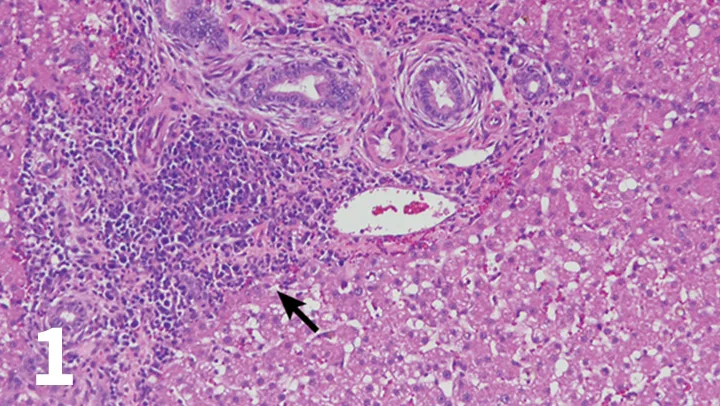

Figure 5

Endoscopic image from a cat with IBD; note the irregular and granular appearance of the duodenal mucosa.

• Endoscopic (Figure 5) or full-thickness biopsy of the GI tract for histopathology may be performed after a therapeutic trial of a limited antigen or hydrolyzed diet for 2 to 3 weeks in milder cases